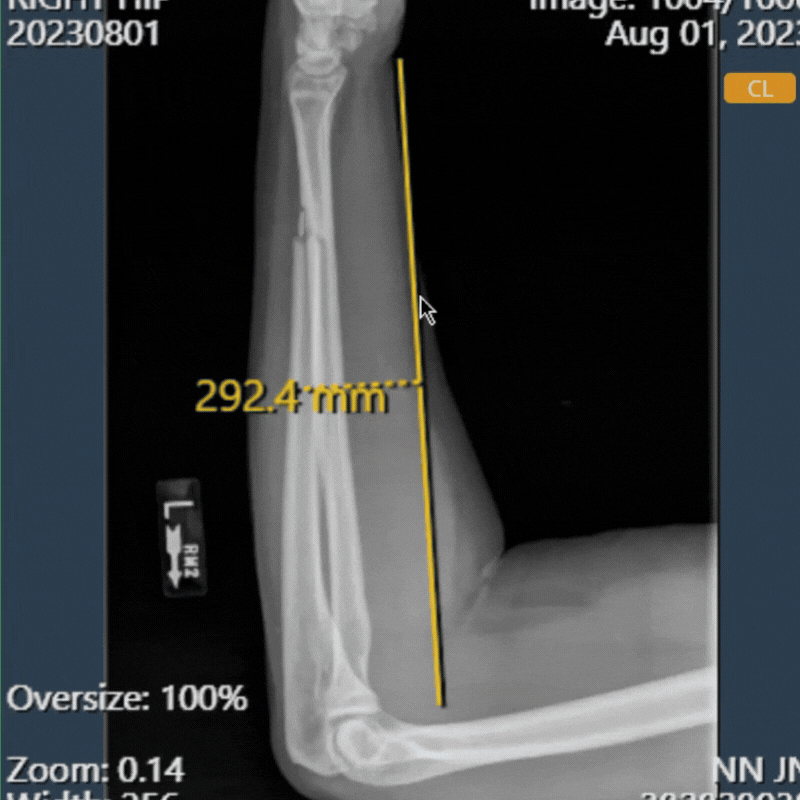

- Additional information was displayed in the size field (HIP): An issue was identified where additional, unrelated information was displayed in the Size field within the information table.